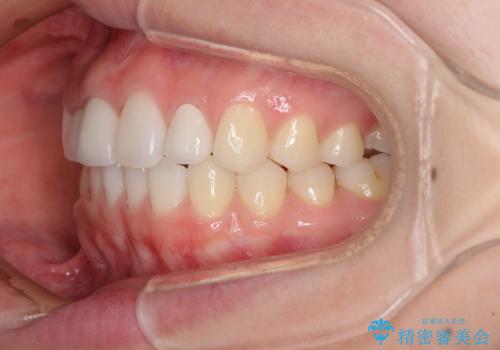

- 前歯の隙間を気にして来院された患者様です。

診察の結果、前歯が1本欠損しており、さらに矮小歯(通常よりも小さい歯)が1本存在していました。

欠損による前歯のスペースが大きかったため、事前にワイヤー矯正で前歯の位置を大きく動かし、その後は上下をインビザラインで整えることとしました。

矯正治療後には欠損部はオールセラミックブリッジに、矮小歯はオールセラミッククラウンにて補綴することとしました。

前歯のスペースは、堅い線維の通った歯肉があり、幅も大きかったことから、歯肉切除を行った上でワイヤー矯正により移動を行いました。また、上唇小帯も歯間部付近まで付着していたため、合わせて切除しました。

ワイヤー矯正により、インビザラインよりも早く、歯軸の向きもコントロールしながら移動させることができました。